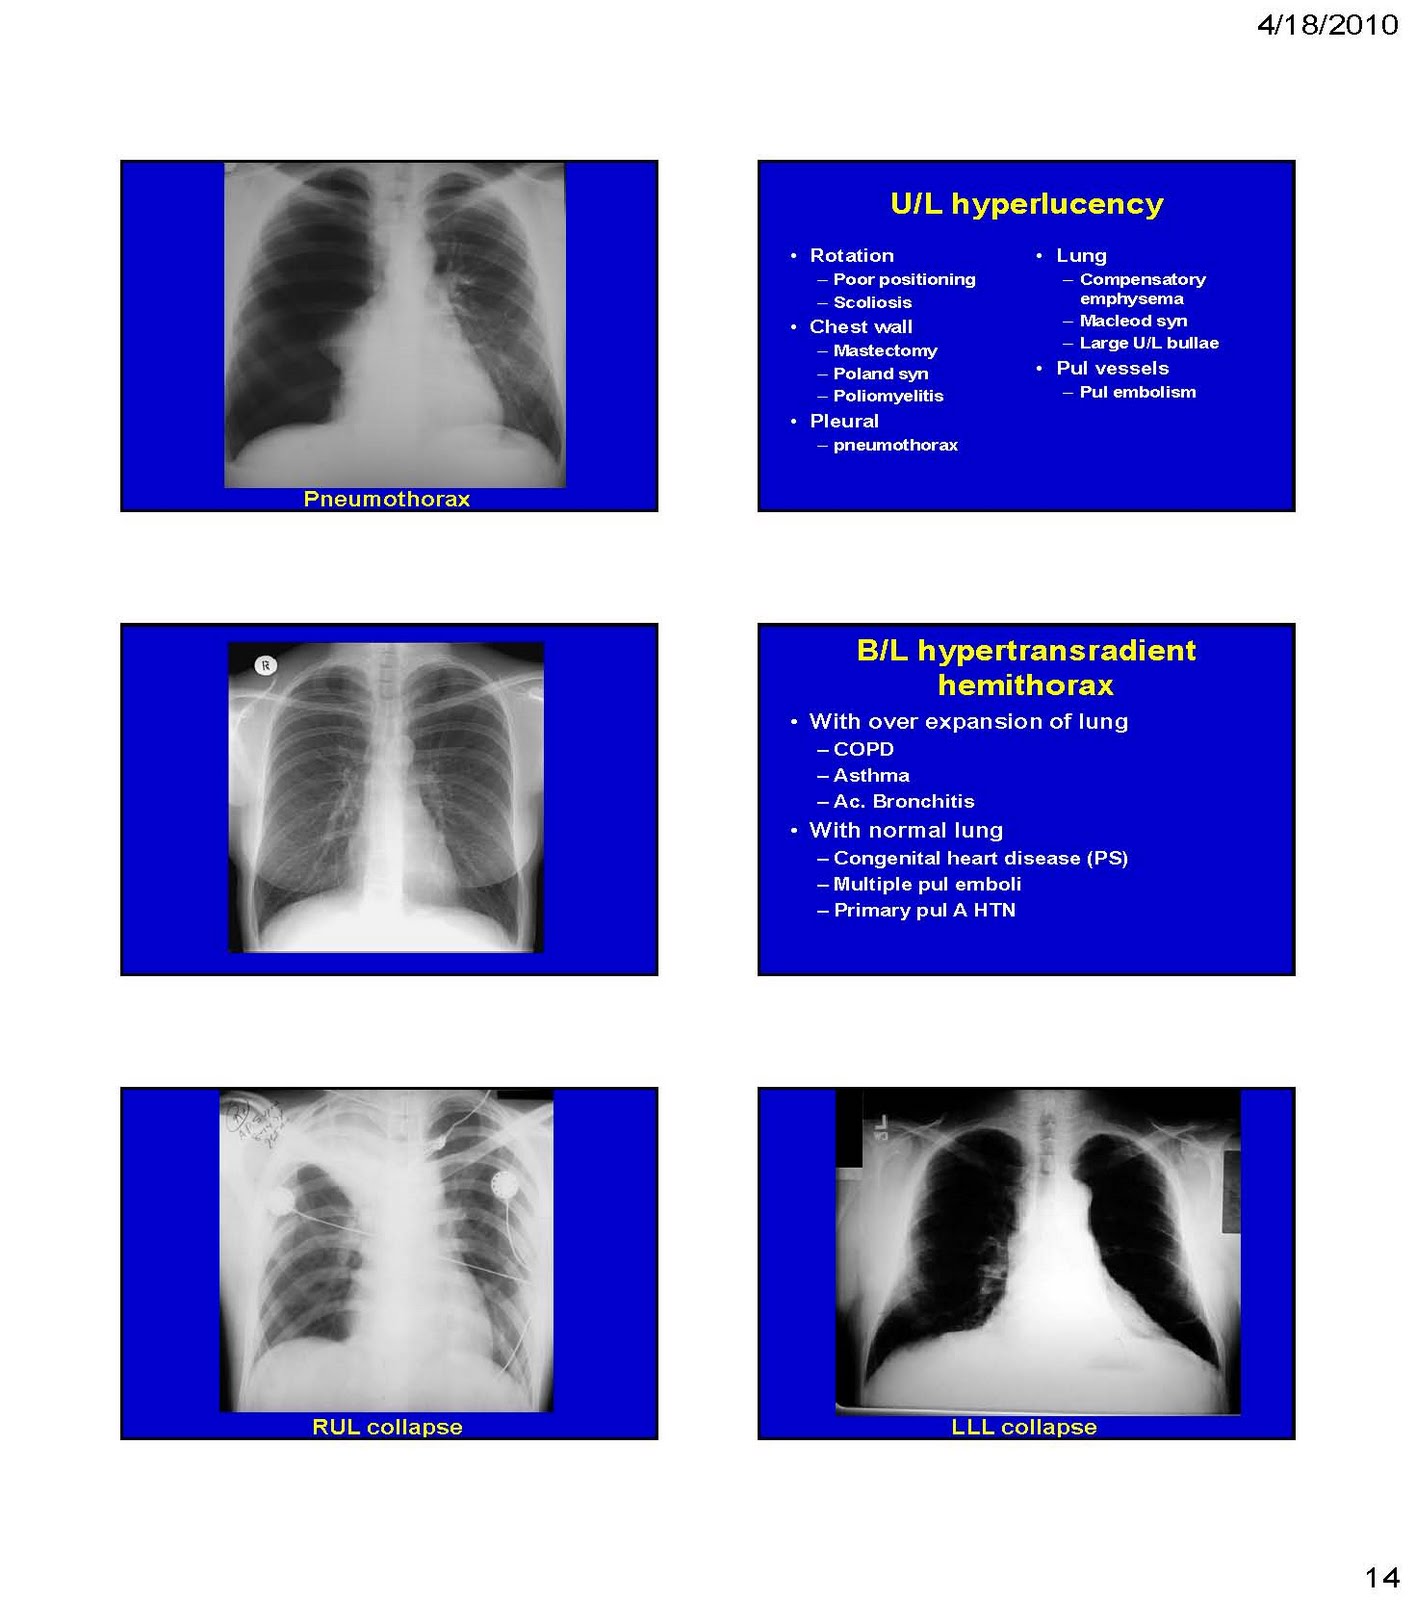

Chest X ray interpretation pulmonary Edema Emphysema tension Respiratory X-Ray Interpretation  It is performed standing and in full inspiration. The chest radiograph remains one of the most commonly performed examinations in radiology. Doctors typically use this procedure to help diagnose breathing difficulties, a bad or. It is typically the first. In fact every radiologst should be an. Respiratory X-Ray Interpretation.